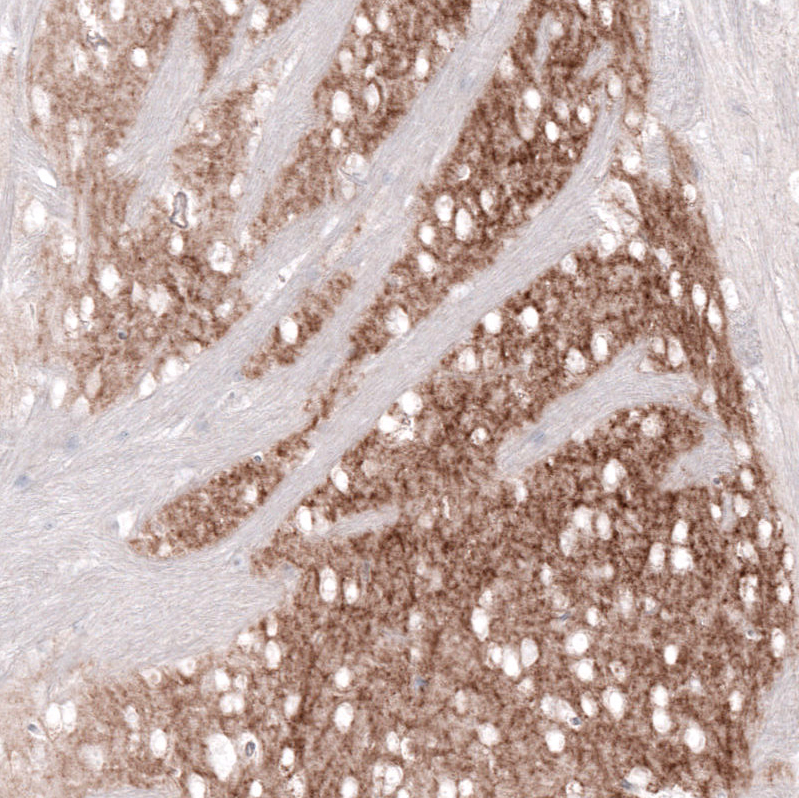

Immunohistochemical staining of rat caudate nucleus shows moderate to strong positivity in neuronal processes.